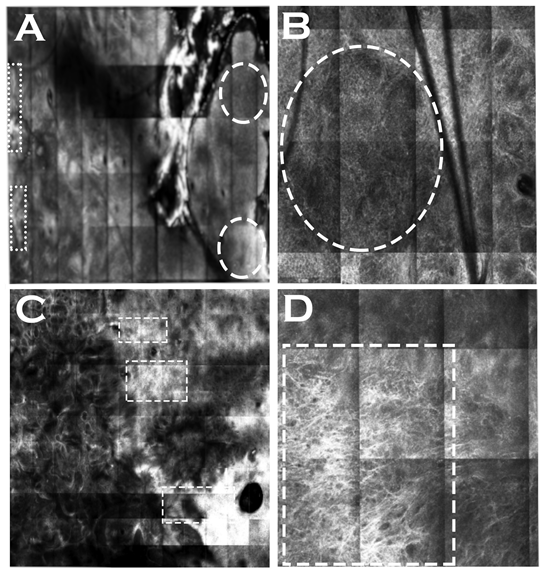

On RCM, cSCCs and AK both display a mildly atypical or disarranged honeycomb pattern [69]. However, cSCCs exhibit increased keratinocyte atypia and architectural disorder [69]. Invasive cSCCs exhibit further architectural disarrangement with atypical cells such as polygonal or round cells with a speckled appearance, prominent dark nucleus in the epidermis, sharply demarcated contours filled with amorphous material, ulceration/erosion, and an absence of hyperkeratosis [70]. Irregularly dilated vessels are associated with invasive cSCC [70]. In contrast, well differentiated or moderately well differentiated cSCCs have some preservation of normal architecture with the presence of speckled nucleated cells within the epidermis [70]. Figure 5 highlights various features of cSCC observed under IVRCM.

Figure 5. In vivo reflectance confocal microscopic (Vivascope 1500®) features of cutaneous squamous cell carcinoma at various levels of depth in the epidermis (cSCC). (A) Atypical honeycomb pattern (represented within oval) with keratinocytic pleomorphism (represented within rectangle). (B) Keratinocytes pleomorphism and epidermal disarray. (C) Keratinocytic atypia/disarray. (D) Atypical keratinocytes.